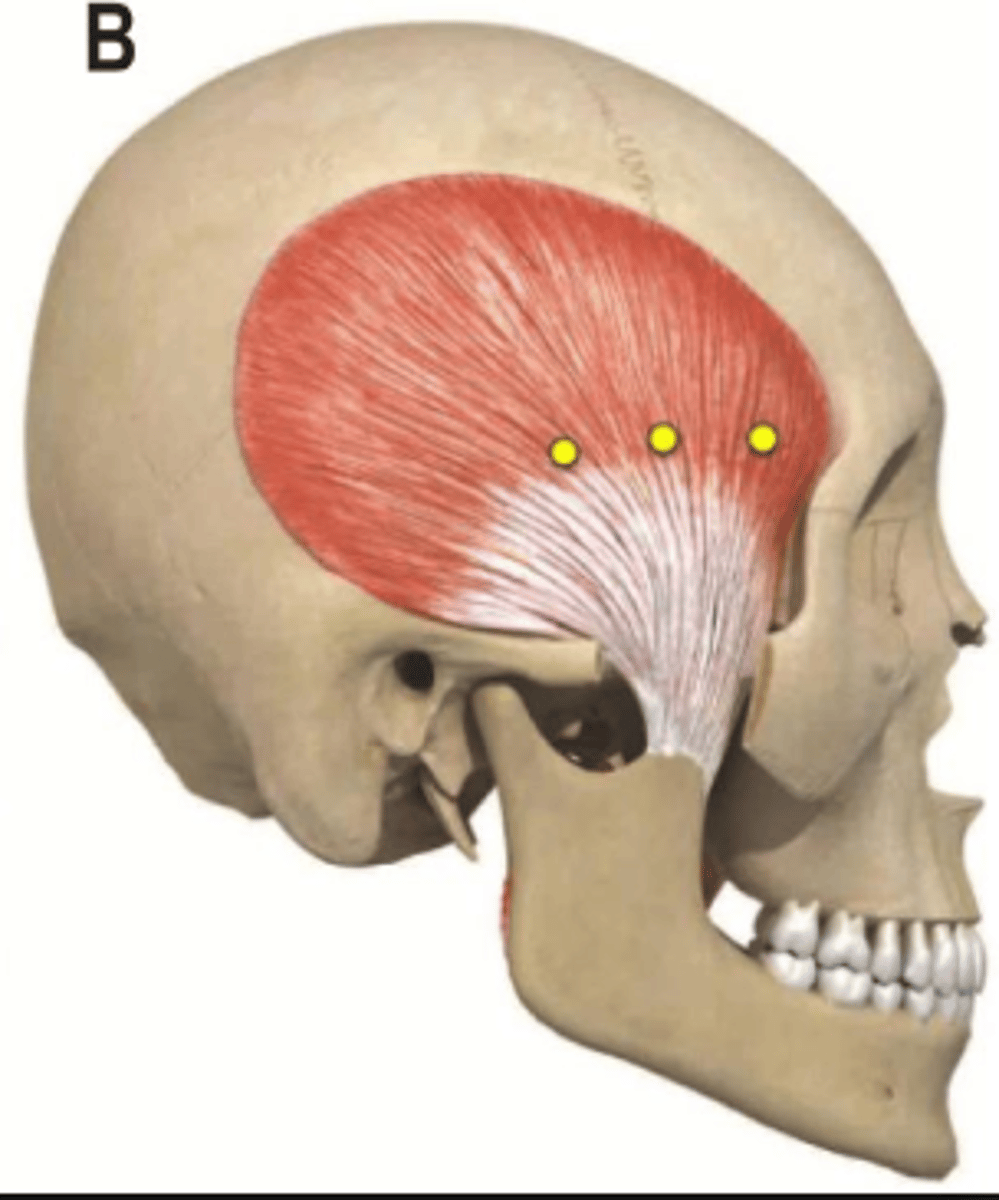

Temporalis m.

Origin: Temporal

Insertion: Coronoid process Action: Elevate